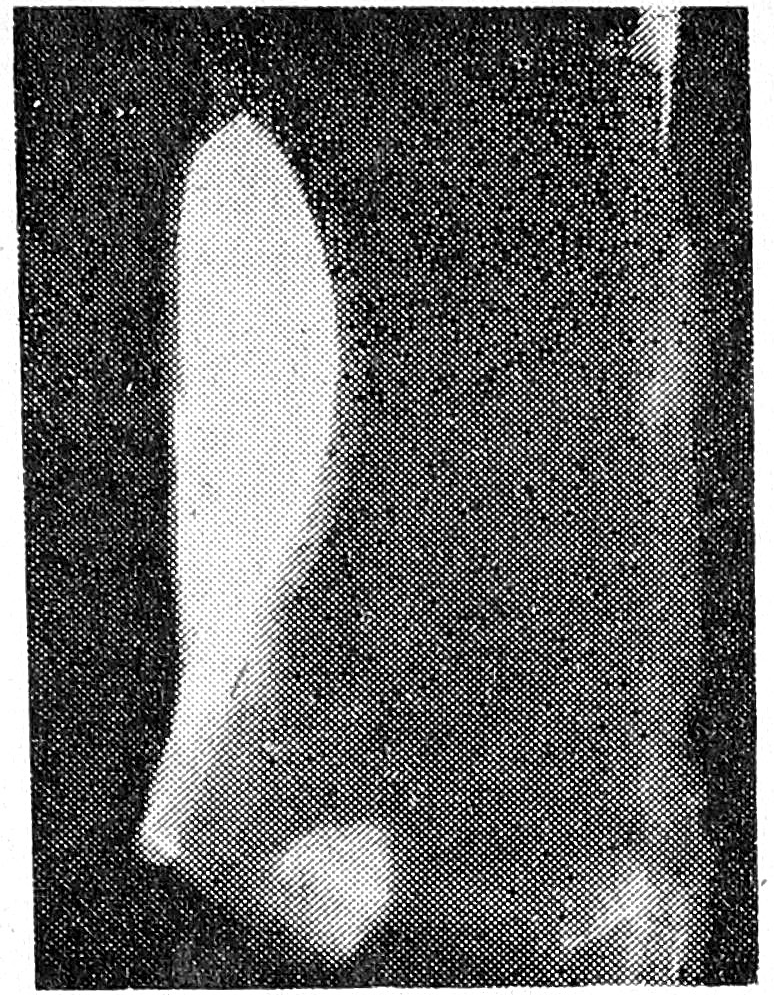

Необходимо особо отметить, что введение большого количества контрастного вещества (до 30 мл) со значительной скоростью (до 15 мл/с), независимо от применяемого типа иглы, приводит к тяжелым повреждениям стенки аорты, заключающимся в разрушении ее интимы, которое обнаруживается даже визуально (рис. 4). К сожалению, при клинической аортографии количество и скорость вводимой за один прием контрастной жидкости строго не регламентируются, учитывается лишь токсическое воздействие ее.

Рис. 4. Фотоснимок препарата аорты с интимой, разрушенной при введении 30 мл контрастного- вещества при скорости 15 мл в секунду (светлые участки).